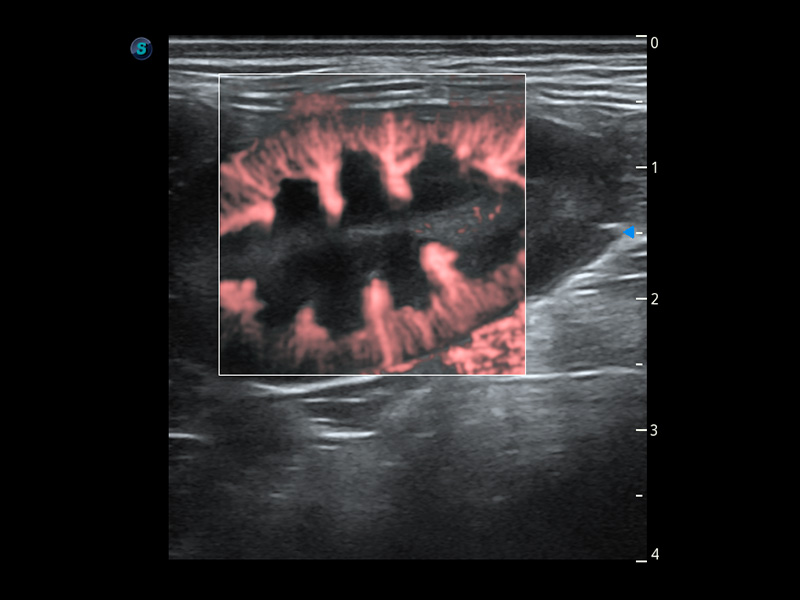

优异的基础图像

(犬)肾脏血流

4T血流成像 微察秋毫

融合不同血流成像技术的优势,即可以提升血流成束性,同时可提高血流的视觉敏感性。

PDI 能量多普勒血流

提供高灵敏度和空间分辦率的血流图像,获得更加真实和丰富的诊断信息。

SR Flow 高分辨率血流成像

能够清晰显示细小、低速血流图像,获取传统彩色多普勒技术难以得到的细节和信息。

Micro F 显微血流成像

通过创新的Matrix E自适应滤波器和超长时间域算法,极大提升超低速微细血流的检出能力,同时更精准地滤除软组织和噪声信号,为兽用医生提供以往无法通过常规血流获得的疾病诊断信息。

Bright Flow 立体血流成像

在传统二维血流成像的基础上,呈现血流的立体感,具有动感的生命力之美。精确区分不同血管的空间关系,提高了血流的视觉敏感性。